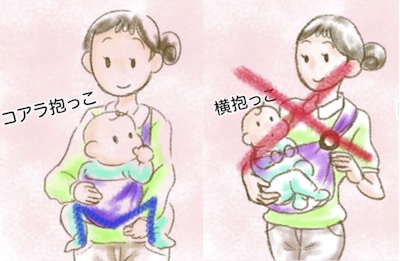

間違った育て方とは(環境因子)

① 股・膝関節を強く伸ばして筋肉を緊張させる。

② 股関節を固定して自由に動けなくする。

この2つがあてはまるような育て方をすると脱臼しやすくなります。単殿位の逆子に脱臼が多いのは①が原因です。おむつの種類や付け方、服の選び方、抱っこのしかた、向き癖への対処などが重要です。詳しくは「脱臼しない育て方」をご参照下さい。

脱臼しない育て方

出生直後の股関節は、臼蓋が浅くて不安定な状態です。その後、骨頭が臼蓋の中で自由に動くことで、臼蓋が深くなり脱臼しない股関節に成長します。上手に臼蓋を育てるためには、股・膝関節を軽く曲げた状態で自由に動かせるようにすること、そして無理に関節を伸ばしたり、固定して動きを制限しないことが大切です。特に出生直後〜2ヶ月までが重要だといわれています。